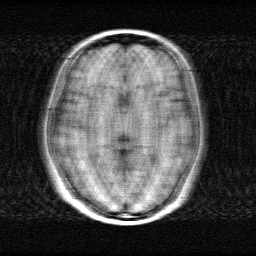

Measurement

Measurement (perturbed)